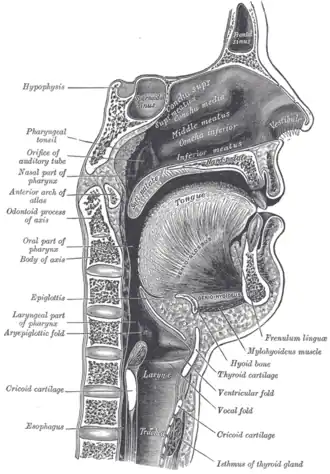

Sagittal section of nose mouth, pharynx, and larynx. (Frenulum linguae is the topmost label at right.) | |